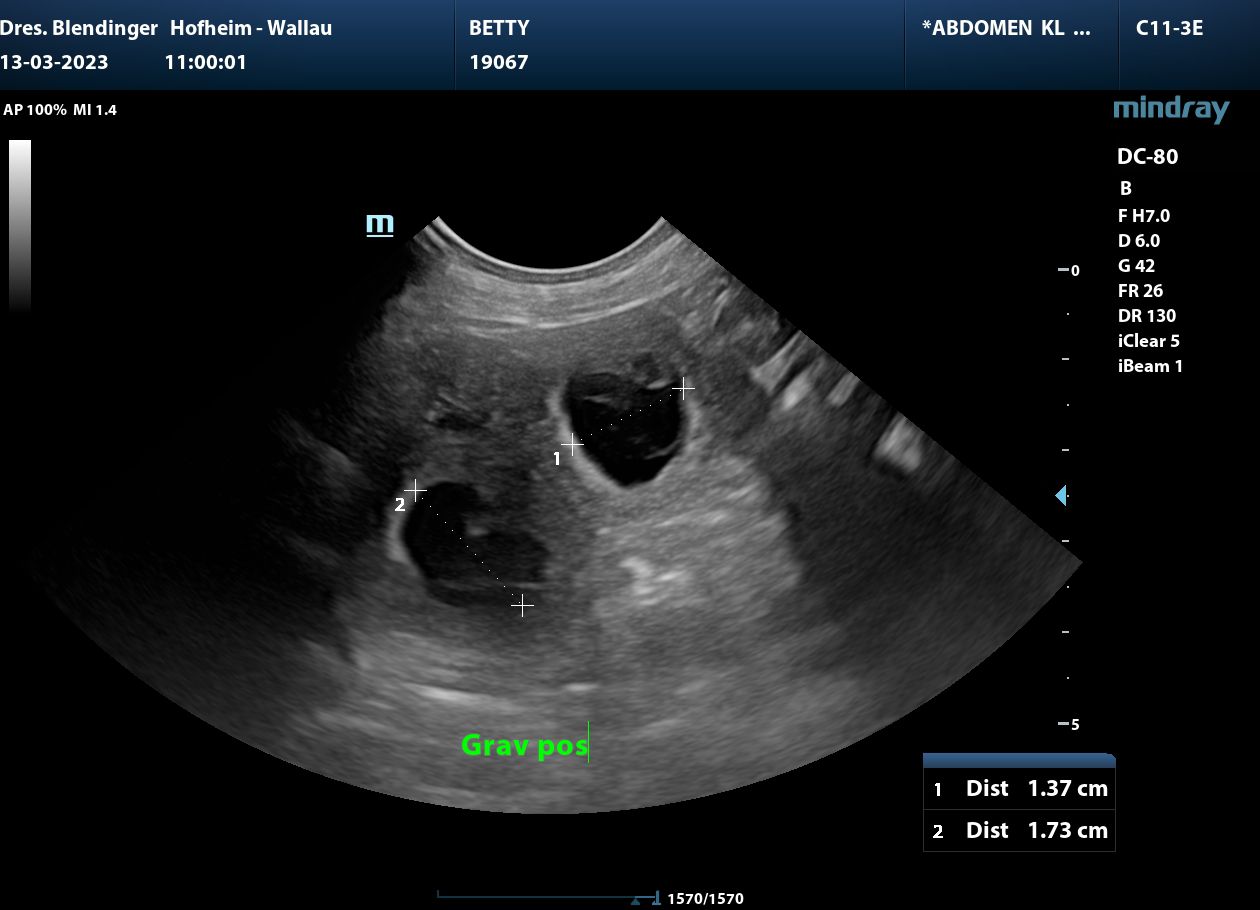

Unsere zauberhafte Betty

und

der Goldschatz Ludwig hatten ein Rendevous.

Wenn die Natur es will, werden Mitte April kleine Glücksbärchen geboren.